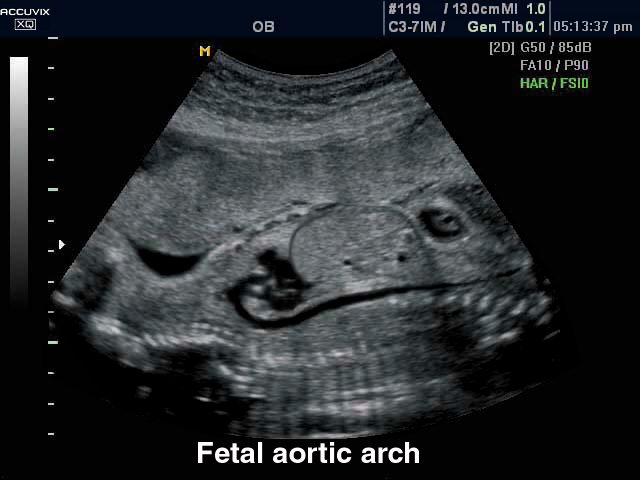

Fetus - arotic arch, B-mode (echogramm №297)

[RU] Ultrasound image №297: Fetus (arotic arch) in B-mode (convex probe 3-7 МГц)

Echogramm was received by ultrasound scanner Accuvix-XQ (out of production).